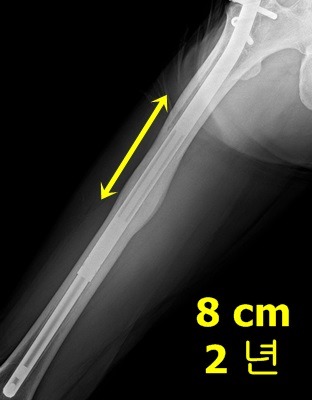

허벅지(ISKD) 8cm 수술후 2년 : 내고정 제거 축하드립니다. 왕자님 ^^